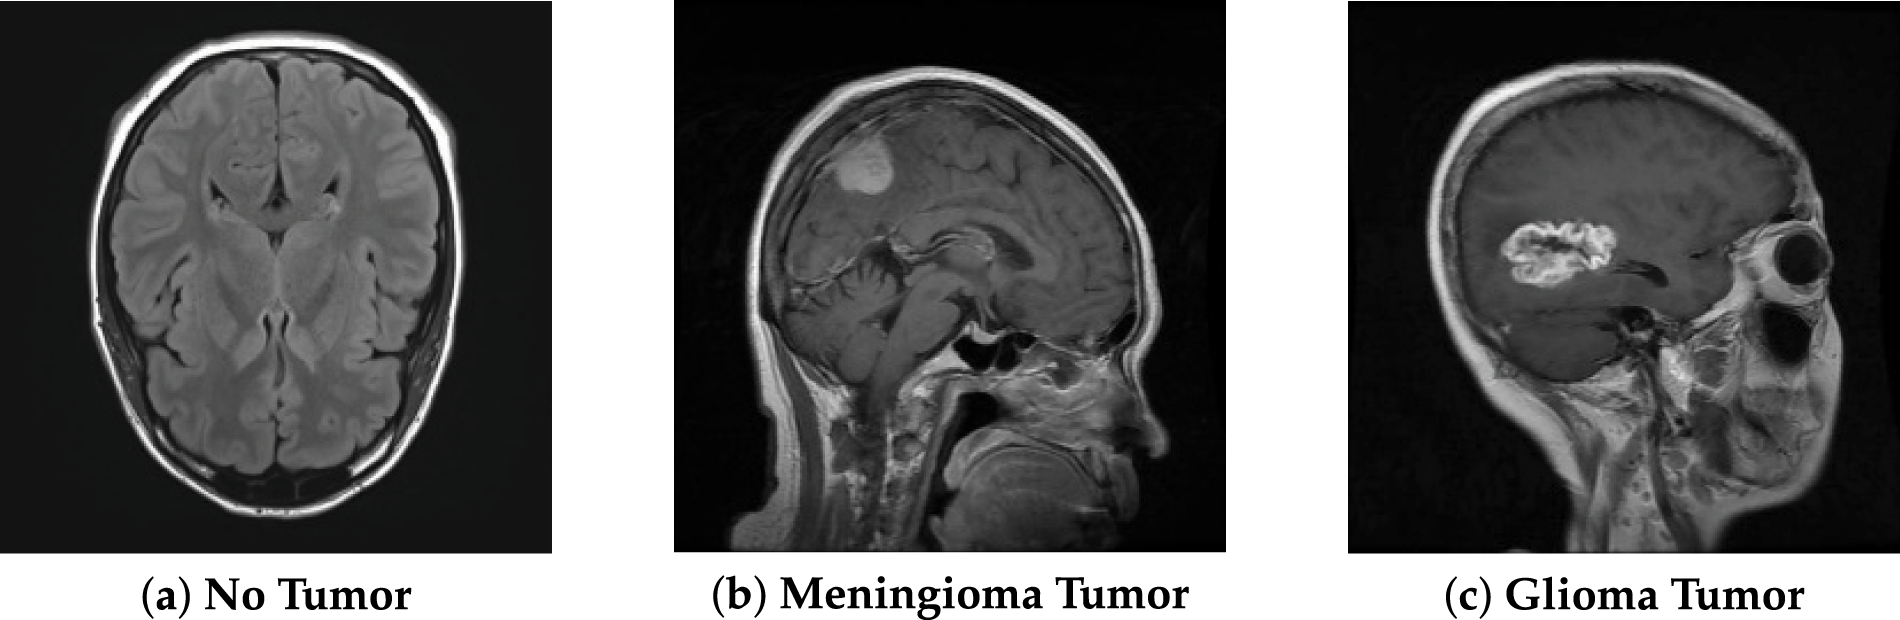

To overcome these problems, image enhancement techniques were developed, such as base–detail layer decomposition combined with adaptive gamma correction, which has been shown to improve CT image visibility without introducing noise or halo artifacts [2]. Image enhancement is one of the primary operations that improves the clarity and visibility of unclear or less visible parts of an image, as well as enhances low contrast. Its main goal is to improve the quality, clarity and to enhance interpretability of images [3]. Contrast enhancement is a crucial part of image improvement. The techniques have changed over time. Among the many methods created over the past few decades, histogram-based techniques stand out due to their computational efficiency and adaptability to different imaging modalities. Fig. 1 shows the MRI images of the brain. We used this dataset to further do analysis (Table 1).

Figure 1: Brain MRI, data from Kaggle [4].